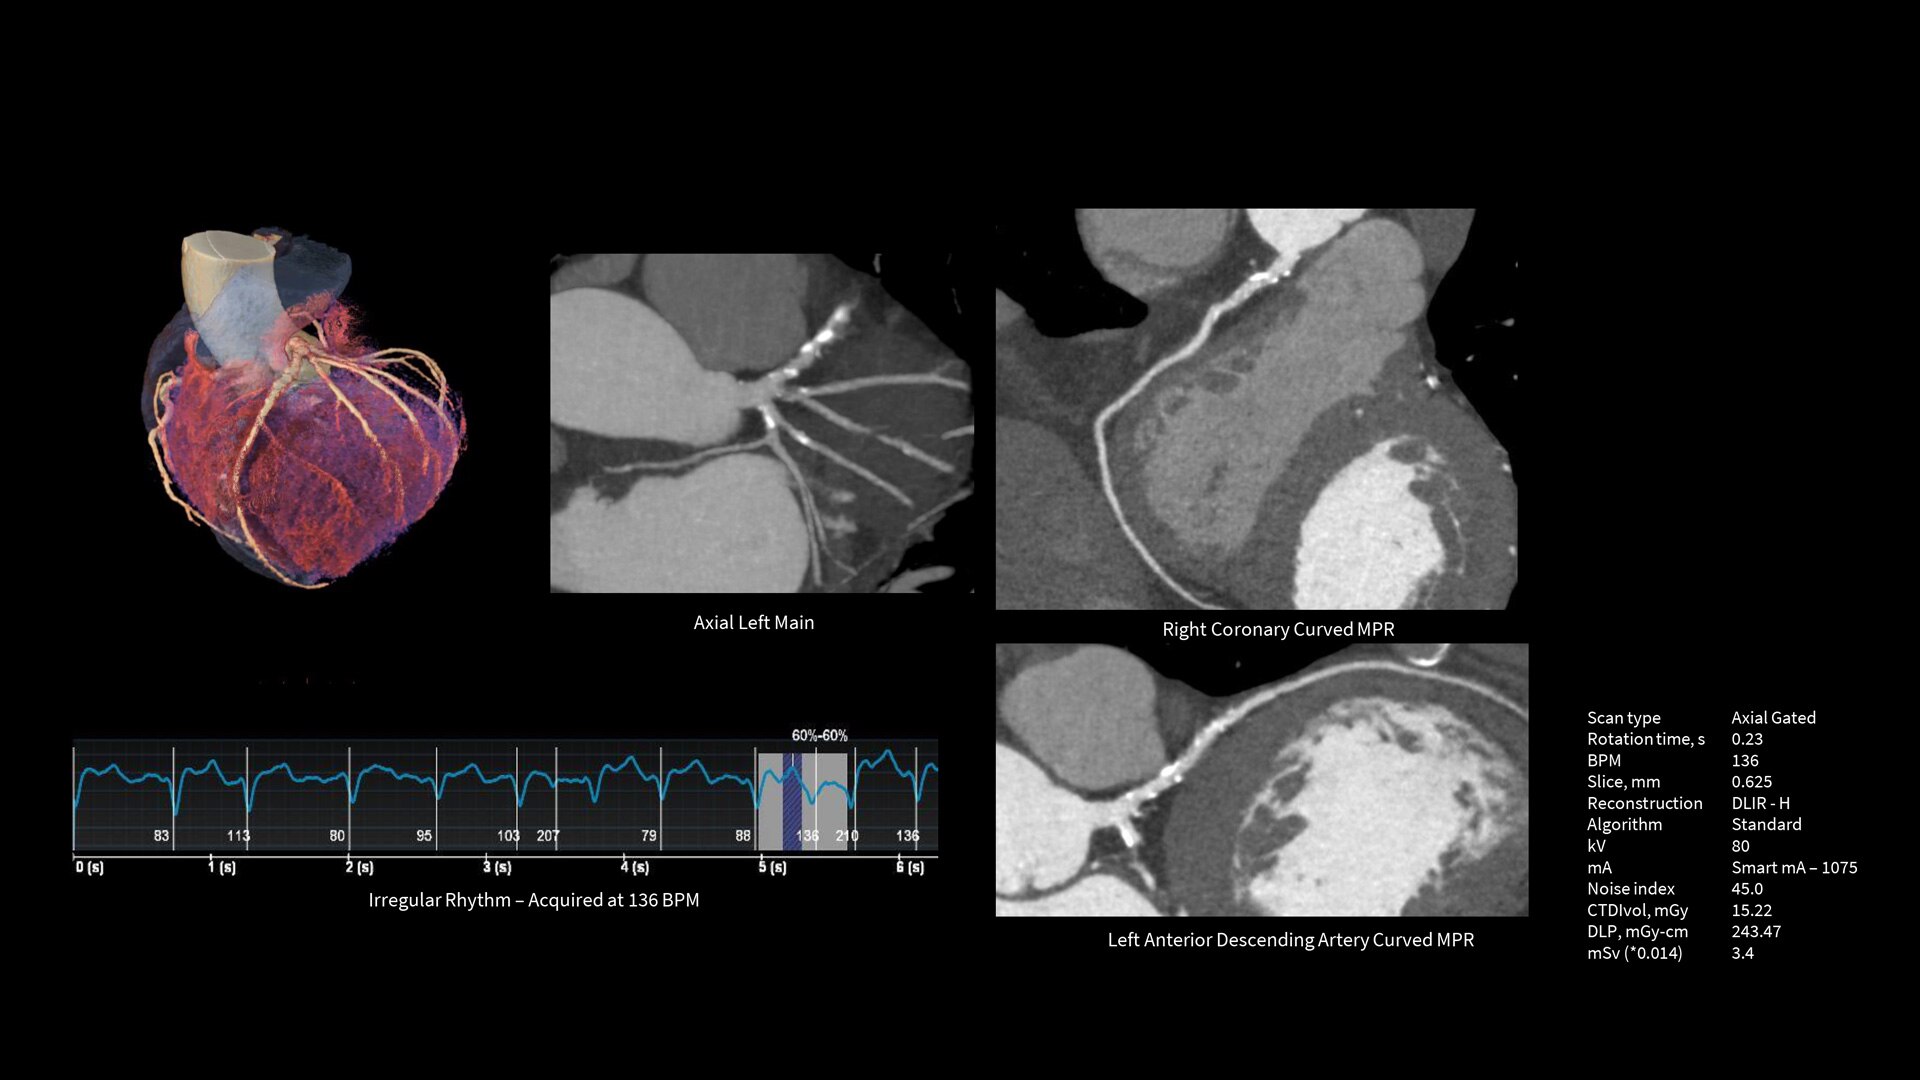

Upgrade to the industry's fastest rotation time

The Revolution Apex platform allows you to upgrade your gantry rotation speed. You can start with 0.28 sec gantry rotation time, and at any point in time when you need to advance your cardiac capability, you can upgrade to 0.23 seconds per rotation with the industry’s fastest rotation time.